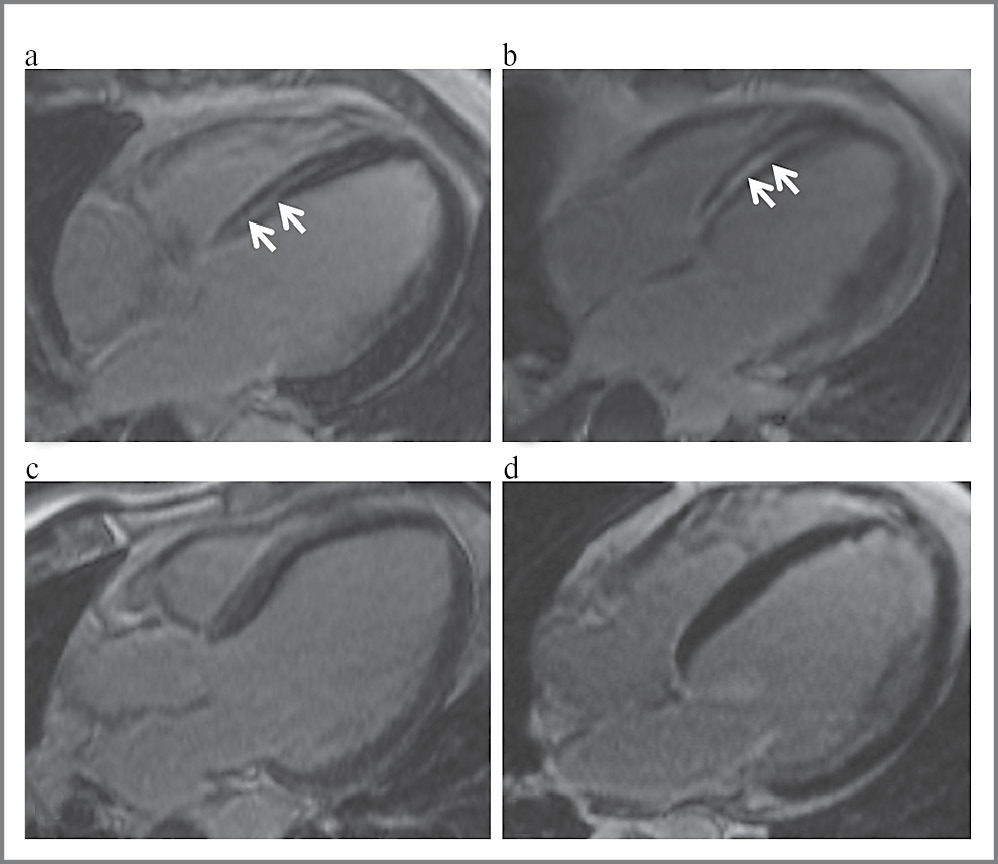

При сопоставлении пациентов 1 и 2-й групп обнаруживался схожий характер очагов ОК (рис. 3). Так, интрамуральное поражение МЖП в виде «стрий» в группах пациентов с ДКМП с БЛНПГ и без БЛНПГ обнаружено в сопоставимом проценте случаев (рис. 3): в 6 (14,6%) случаях в 1-й группе и в 7 (22%) случаях во 2-й группе (p=0,12) и не обнаруживалось у пациентов с идиопатической БЛНПГ (3-я группа).

Рис. 3. Изображения МРТ с ОК, 4-камерная длинная ось ЛЖ: a, c – пациенты 1-й группы (ДКМП с БЛПНГ); b, d – пациенты 2-й группы (ДКМП без БЛНПГ); a, b – отмечается однотипное очаговое накопление контрастного препарата по типу «стрии» в МЖП (указано стрелками); c, d – пациенты без признаков очагового накопления контрастного препарата в миокарде.

Кроме того, пациенты 1 и 2-й групп также статистически значимо не различались по наличию субэпикардиальных очагов фиброза нижне-боковой локализации. Это позволяет предположить, что очаговый фиброз миокарда, в том числе локализованный в МЖП, не всегда является необходимым условием для формирования БЛНПГ как у пациентов с таким тяжелым органическим поражением сердца, как ДКМП, так и у больных без признаков органического поражения сердечно-сосудистой системы.